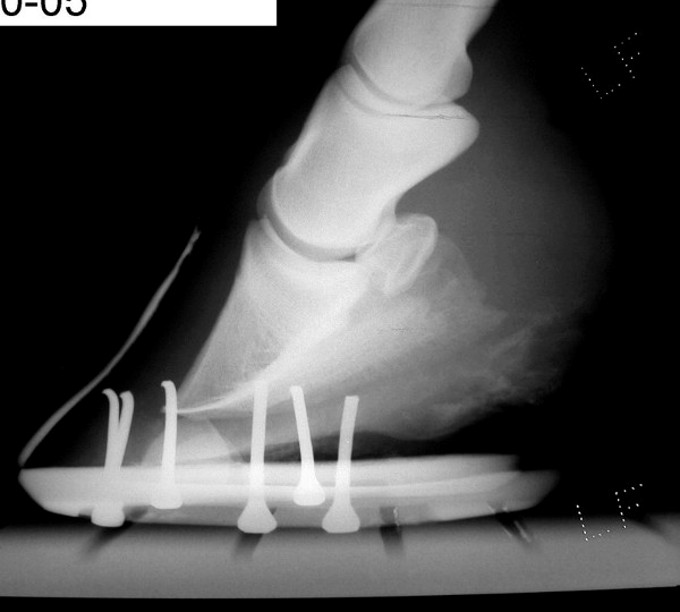

His initial founder was roughly 8 years ago, reason unknown. the rescue group that i adopted him from was told there was no rotation. I adopted him 3 years ago, and our first xrays showed rotation to be roughly 5 degrees in his right front, and 15 degrees in his left. when i got him, he was in plain steel shoes, with pads. the pads were removed due to a bad case of thrush.

we have xrayed every year, just to keep an eye on things. i keep him in plain alumninum shoes, with no pads, this helps me stay ahead of the thrush. the farrier usually did his feet every 6-8 weeks, but this past winter i started having them done every 5... we xrayed in oct 2005. vet says that his rf is at 0 and his left is at 5 degrees. this change in rotation is not due to any corrective shoeing, my farrier has just been following his feet. somewhere, someone (my vet or farrier) mentioned that he may be slightly club foot on his left.

i am attaching xrays and photos of his left front. xrays are from 10/05 and 6/06. photos are from 6/06.

Certainly many of the problems you describe are related to the conformation of the front feet and if I understand your post properly I disagree with your veterinarians assessment of the degree of rotation of the coffin bone in each of the radiographs above. He is apparently drawing a line from the proximal wall rather than looking at the distal wall or the relationship with the ground. I would calculate the difference of the measured angle of the bottom of the coffin bone with a more normal 6 degree tilt and call that the degree of rotation.

Here is the problem: is this rotation because of past founder or because of primary flexor contracture (ie club feet). The two will look similar at this point though the upright pasterns may tip the scales a bit to flexor contracture. If it is decided it is the former, much can be done to return these feet to normal. It it is the latter we are stuck with this.

Hi Dr. O. So you would estimate this to currently be a 6 degree rotation? my vet estimates it to be roughly 5.

No I am not saying it is 6 degrees of rotation but by using the normal tilt of 4 to 6 degrees and subtracting the measured angle you can get a truer picture of the amount of rotation you have. And not the trim so much responsible as past founder vs DDF contracture. Though I lean toward the latter for the reasons given above.